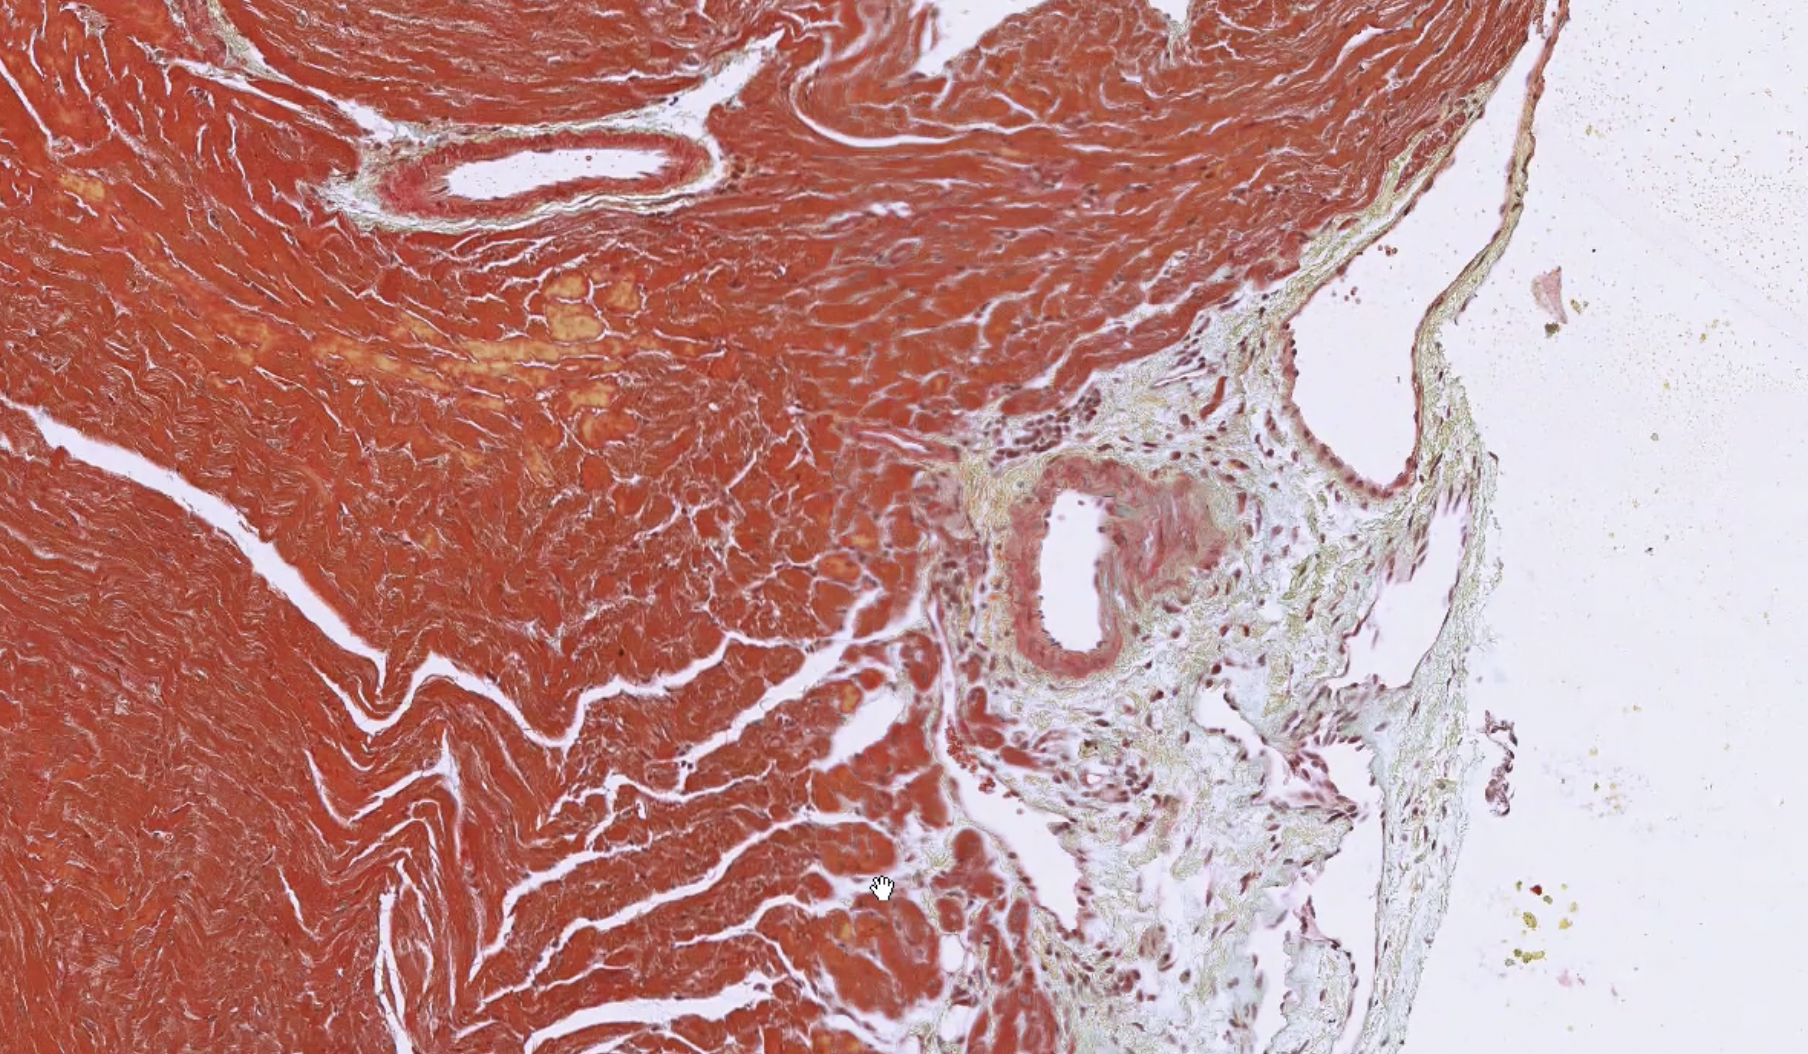

Heart_Pen_02.svs Heart_Pen_02.png |

The pentachrome staining of the stroma (green/blue) is well visualized. The pentachrome red staining of the muscles helps to differentiate between the type of blood vessels present as the arterial vessels are surrounded by muscle and the venous blood vessels are not. The striations of the cardiomyocytes are also well visualized with the pentachrome stain kit.

Please note: contraction bands can look fractured, but the appearance presented is dependent on the state of contraction when the tissue is excised and fixed.